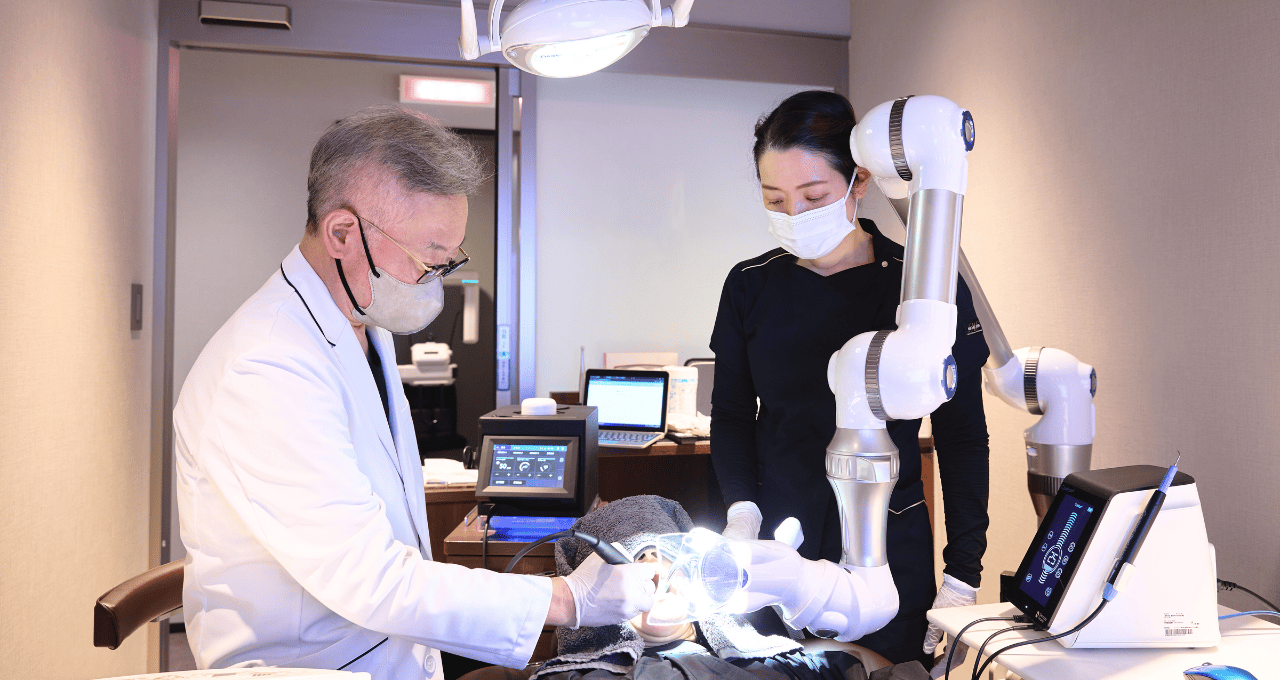

開発者・菅野太郎教授の理念への共感

この治療法は東北大学大学院歯学研究科の菅野太郎教授を中心とした研究グループによって開発された世界でも先進的な技術です。科学的根拠に基づき、患者様の負担を小限に抑えながら大限の効果を追求する。その開発理念は私が目指す歯科医療の理想と完全に一致するものでした。

私はこれこそが歯周病に苦しむ多くの方々を救う「新しい光」になると確信し、導入を決めました。

「ブルーラジカル治療」の仕組みと力

それでは当院の歯周病治療の核となる「ブルーラジカル治療」について、その仕組みを詳しくご説明します。

光で細菌を殺菌する「光殺菌治療(PDT)」とは

ブルーラジカル治療は専門的には「光殺菌治療(PDT: Photo-Dynamic Therapy)」と呼ばれる治療法の一種です。

これは光に反応する特殊な薬剤と特定の波長の光線を組み合わせることで、細菌などの標的だけを破壊する治療法で、歯科以外の医療分野でも応用が進んでいます。

ブルーラジカル治療の具体的な流れ

| ステップ | 内容 | 特徴 |

| Step1 | 歯周ポケットへの光感受性ジェルの注入 | 殺菌したい歯周ポケットの中に「光感受性ジェル」という特殊なジェルを丁寧に注入。痛みは全くありません。 |

| Step2 | 安全な青色光(405nm)の照射 | 専用の機器「ブルーラジカルP-01」の先端から安全な青色光を歯周ポケット内に照射。熱さや痛みを感じることはほとんどありません。 |

| Step3 | フリーラジカルの発生と殺菌作用 | 光のエネルギーを受けたジェルは化学反応を起こし、極めて殺菌力の高い物質「フリーラジカル」を大量に発生させます。 |